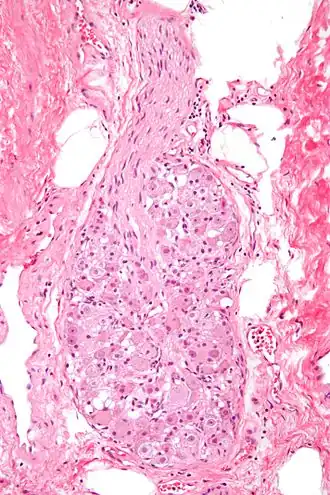

Micrograph of a ganglion. H&E stain.